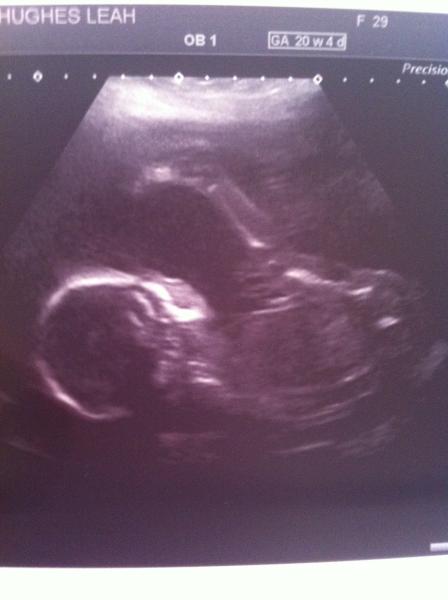

Congrats on the scan Madem. So exciting.